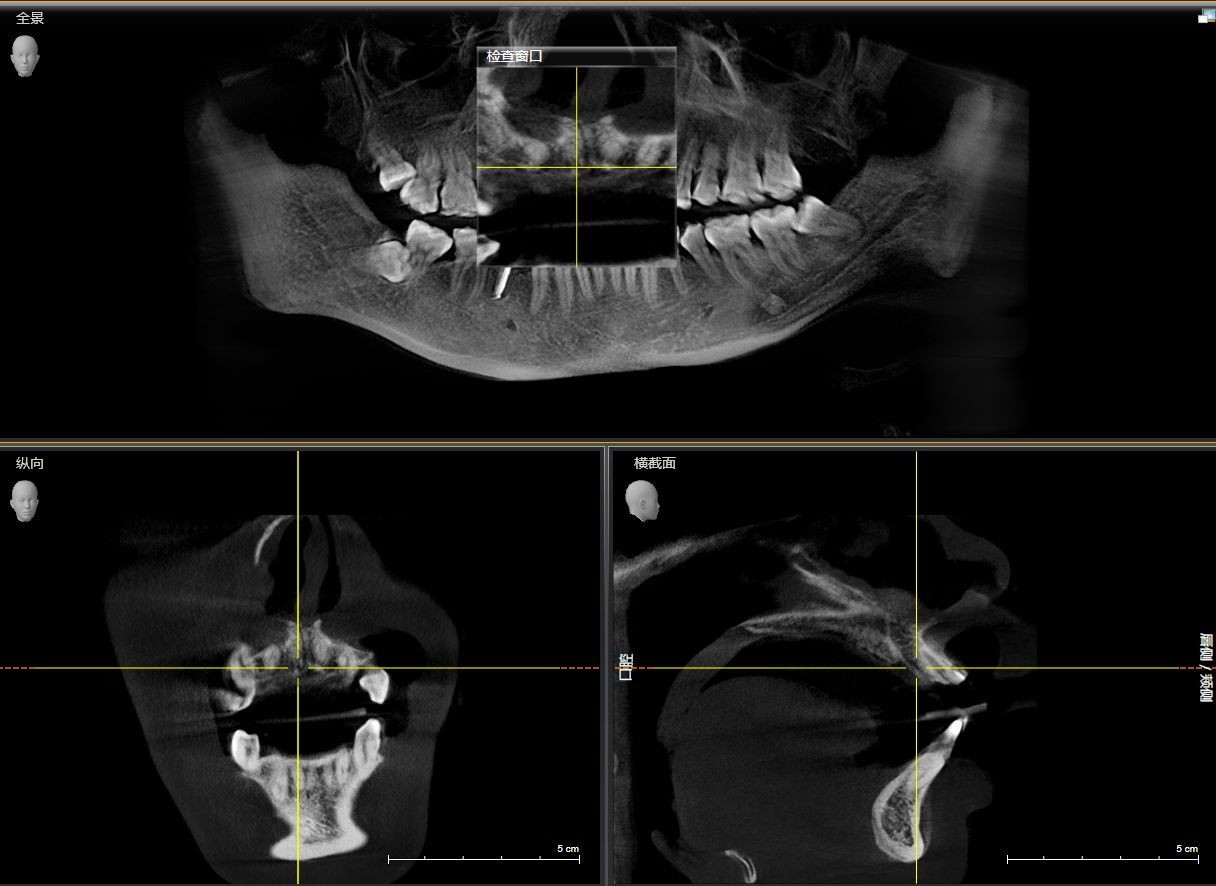

患者右上中切牙外伤导致冠根折,腭侧折面至骨下2mm,需要拔除患牙,x片显示唇腭侧牙槽骨完整,唇侧牙槽骨厚度1.5mm,根尖区剩余牙槽骨也有8mm,符合即拔即种即修复基本条件,患者知情同意下,术前两小时CEREC数字化扫描,设计种植导板,术前准备,拔除患牙,种植导板精密就位,种植窝完成制备,植入植体,拔牙窝间隙中植入Bio-oss骨粉,放置扫描杆,CEREC数字化扫描,一小时后即有一颗和左侧中切牙形态,颜色一致的右侧中切牙,不需要缝合,术后无疼痛,患者非常满意,CEREC数字化技术带给你无限可能!